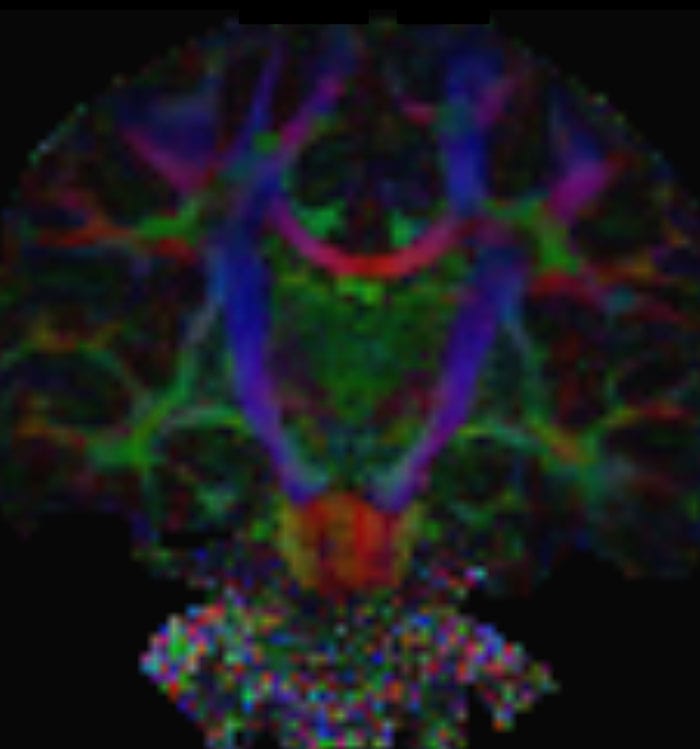

These images are produced using the ABCD protocol and illustrate the use of more sophisticated and accurate models of diffusion. The color FA maps are shown for reference. The diffusion tensor model represents the diffusion within each voxel as an ellipsoid.

Alternative models, such as constrained spherical deconvolution, better capture the rich information available with the use of high b-value dMRI and many sampling directions. In much of the brain, voxels contain multiple white matter tracts, and it is essential to capture this information to be able to perform accurate tractography and generate diffusion connectomes.

Diffusion acquisition on Achieva 3.0T dStream with matrix 140x141, 81 slices, FOV 240x240 mm, voxels 1.7x1.7x1.7 mm, TR 5300 ms, TE 89 ms, flip angle 78, MultiBand SENSE factor 3, partial Fourier 0.645, 102 diffusion directions, b-values 0 (6), 500 (6), 1000 (15), 2000 (15), 3000 (60) , scan time 2x 4:37 min. Images provided by Dr. Watts.